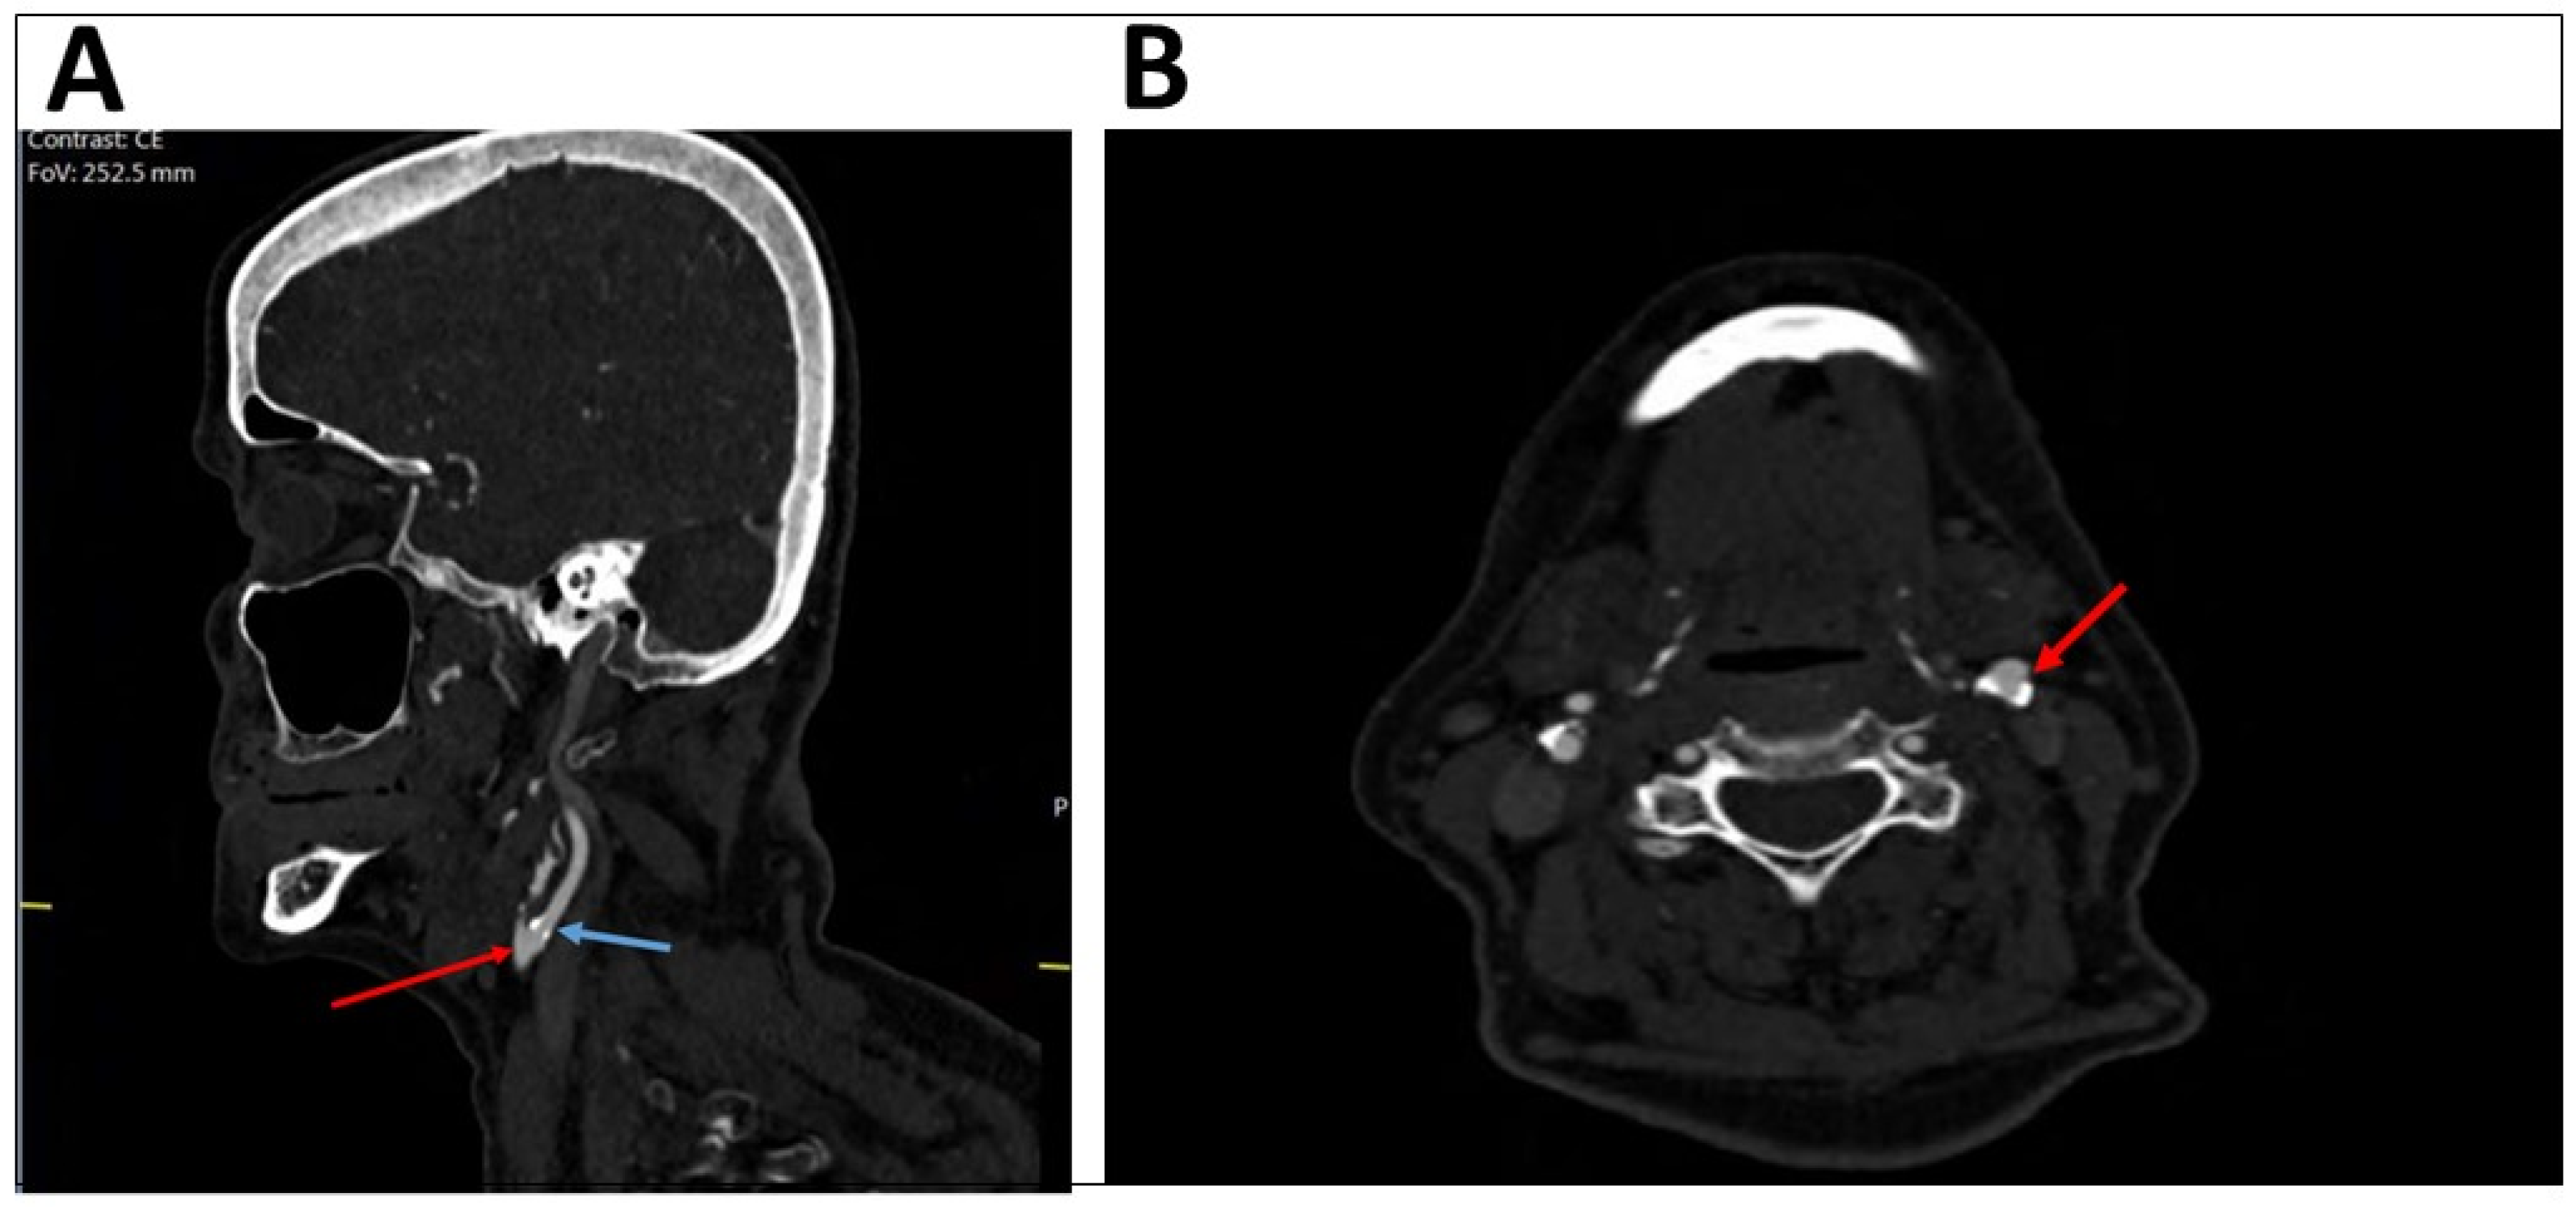

Figure 2.

CT angiography showing the same patient with mild stenosis of the left internal carotid artery. The sagittal plan (A) presents the left common carotid artery (bulb, red arrow) and the left internal carotid artery (blue arrow). The axial plan (B) shows mild stenosis of the left internal carotid artery (red arrow).